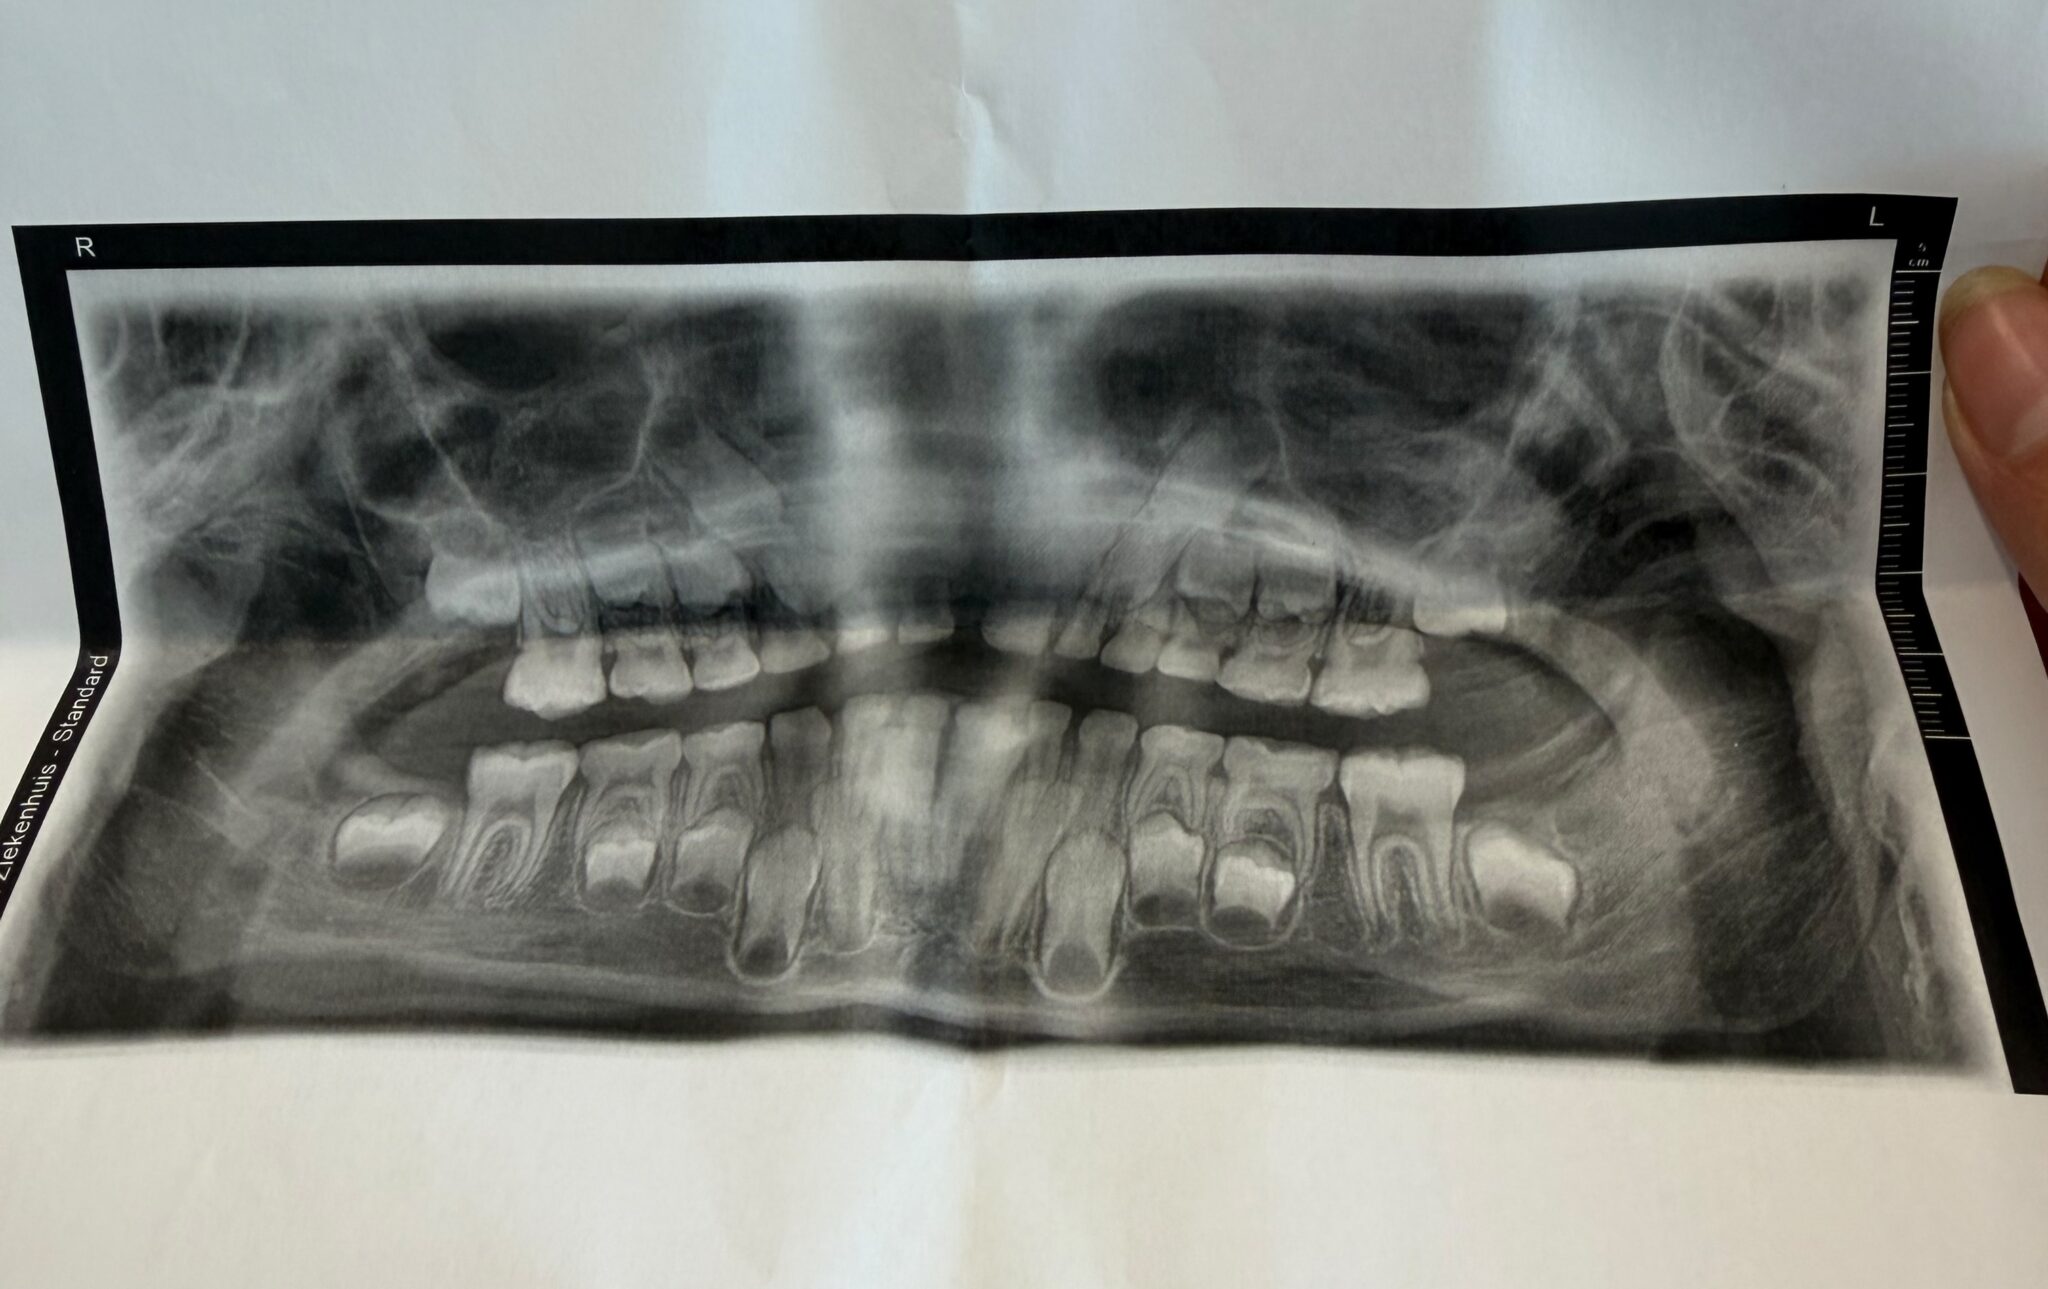

Kleefstra syndroom en het gebit, van de eerste tandjes tot ontbrekende volwassen tanden

Hoe het Kleefstra syndroom invloed kan hebben op het gebit Het Kleefstra-syndroom is een zeldzame genetische aandoening die invloed heeft op verschillende onderdelen van de ontwikkeling. Maar wist je dat ook het gebit zich vaak anders ontwikkelt dan bij een normaal kind? Dat kan al beginnen bij de eerste tandjes. Sommige kinderen met het Kleefstra … Meer lezen over Kleefstra syndroom en het gebit, van de eerste tandjes tot ontbrekende volwassen tanden